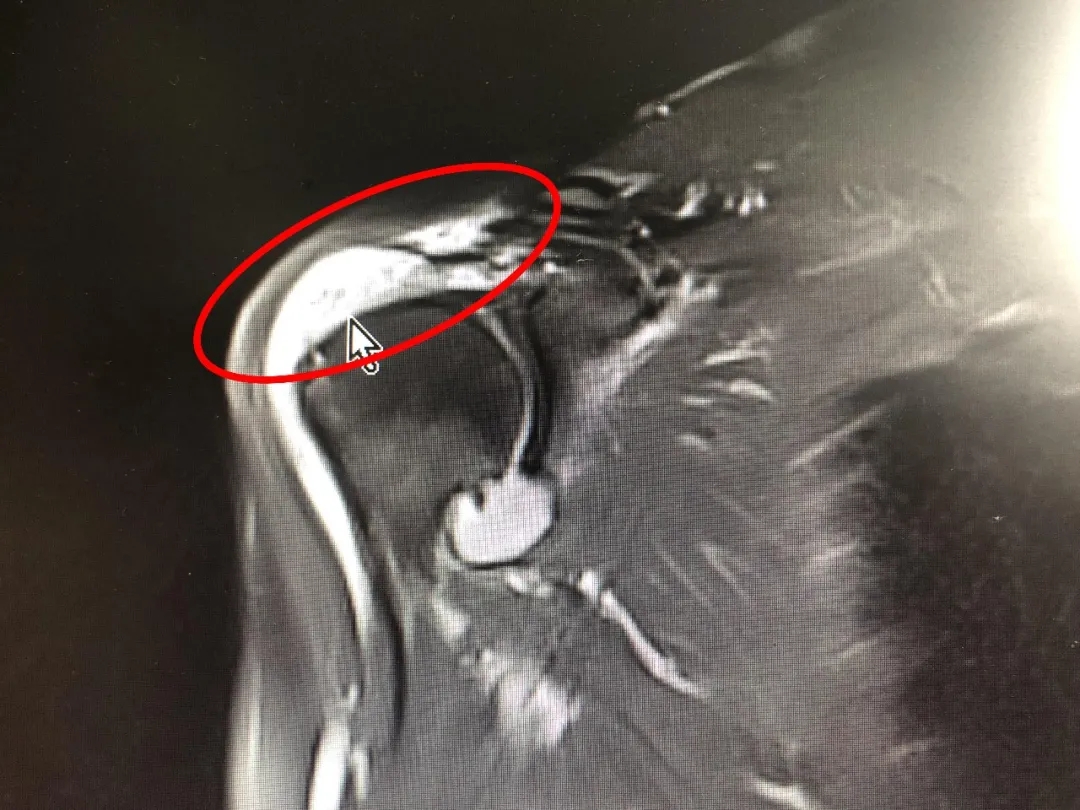

58岁的田女士四年前右肩部受过伤,最近右肩关节疼得厉害,胳膊也无法抬起,来到我院骨科就诊,磁共振检查显示“巨大肩袖撕裂,肩袖严重回缩”。 术前影像资料 经过充分术前讨论,骨科二病区医疗团队决定为患者实施肩关节镜微创治疗。术中探查发现,患者肩袖回缩严重,不适合直接修复,遂采用“Chinese Way”术式完成肩关节镜下肌腱重建。术后三个月复查,患者右臂活动自如,肌腱位置良好。 术后3个月复查影像资料 骨科二病区主治医师孙卓伟介绍:“不可修复的巨大肩袖撕裂,治疗时需要考虑很多因素,由于肌腱变性、肌肉脂肪浸润、肌腱的过度回缩导致肌腱质量比较差,手术难度系数极大,怎样在关节镜下缝合肌腱以达到更好的效果,对于手术医师来说也充满了挑战。” 医师提醒 肩袖撕裂后首先要减少导致疼痛的动作,不刺激患处,若疼痛时间较长,症状严重,建议尽快来院就诊,尽早恢复肩关节功能。 关节镜微创技术相较于传统手术,具有切口小、感染率低、恢复快,住院时间短等优点。 骨科二病区2019年起开展肩关节镜微创技术,截至目前开展手术100余例,均取得了良好效果。科室独立开展巨大肩袖撕裂、肩峰撞击、关节内游离体、钙化性肌腱炎,肱二头肌病变等肩关节疾病手术诊疗。 联系电话: 0533-8228176 就诊地址: 门诊楼二楼外科诊区 住院部7楼西